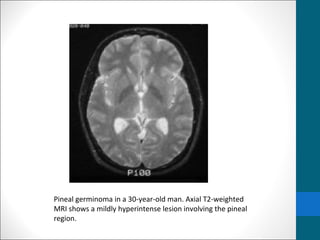

Pineal germinoma in a 30-year-old man. Axial T2-weighted

MRI shows a mildly hyperintense lesion involving the pineal

region.

Germinoma …..MRI findings •T1/T2: • Usually isointense relative to cerebral gray matter •Occasionally • T1:hypointense • T2:hyperintense • I/V injection of gadolinium-based contrast material, • homogeneous and intense enhancement is seen. • contrast-enhanced MRI (subarachnoid seeding of germinomas.)